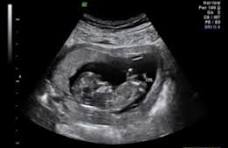

USG 2D: Kenali 5 Manfaatnya untuk Kesehatan Janin Anda

Momen kehamilan adalah salah satu fase paling menakjubkan dalam hidup. Setiap calon orang tua pasti ingin memastikan bahwa si kecil di dalam kandungan tumbuh dengan sehat dan sempurna. Salah satu cara terbaik untuk memantau perkembangan ini adalah melalui pemeriksaan USG 2D atau ultrasound 2 dimensi. Meski kini tersedia teknologi yang lebih canggih seperti USG 3D … Read more